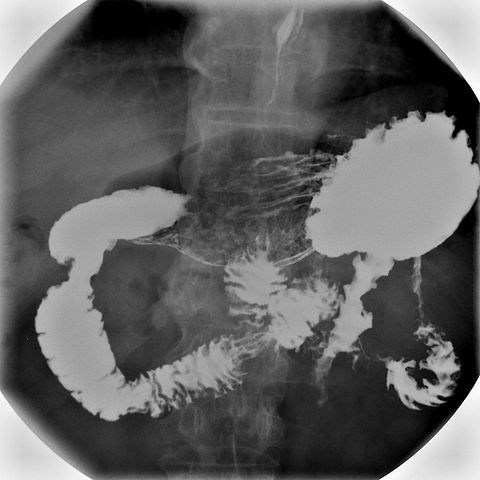

Doctors often need to use X-rays to look inside the intestine and the stomach for cancers, ulcers and blockages.

However, using X-rays to diagnose

such conditions does pose a problem, because the stomach and the intestine are

transparent to X-rays (they pass through), so no image is detected – unlike

bone, which is opaque to X-rays. To overcome this, doctors give their patients

a barium meal that contains insoluble barium sulphate and water. The stomach

and intestine become coated with the barium sulphate, which is opaque to

X-rays, and so a shadow of these organs is cast on an X-ray photographic film.